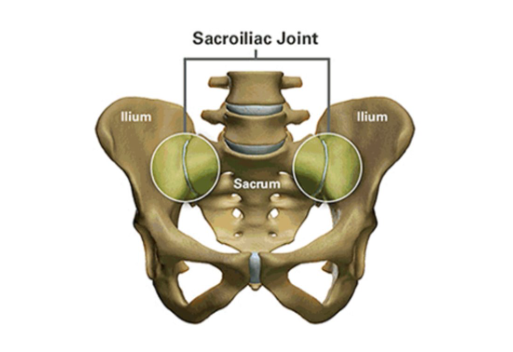

Sacroiliac Joint (SI Joint) Anatomy

The sacroiliac joint (SI joint) is located in the pelvis; it links the iliac bones (pelvis) to the sacrum (lowest part of the spine above the tailbone). It is an essential component for energy transfer between the legs and the torso.

Like any other joint in the body, the SI joint can be injured and/or undergo degeneration. When this happens, people can feel pain in their buttock and sometimes in the lower back, hips and legs. This is especially true while lifting, running, walking or even lying on the involved side.

It’s common for pain from the SI joint to feel like disc or lower back pain, or sometimes hip or groin pain. For this reason, SI joint disorders should always be considered in lower back, hip, and pelvic pain diagnosis.